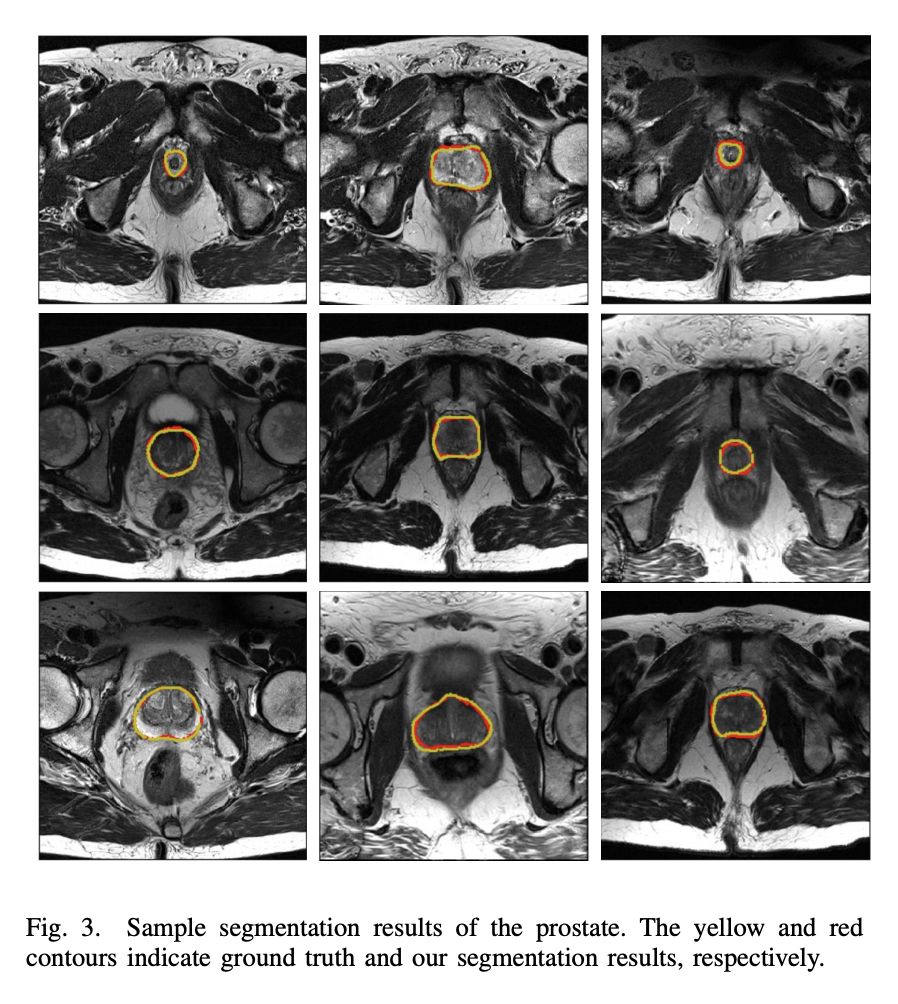

#Image Segmentation

本文提出了一种新的分割网络——BOWDA Net。基于此网络,作者在 MICCAI 2012 前列腺分割竞赛中排行第一,结果为 state of the art。创新点有两点:1)针对前列腺 MR 图像边界不清晰的问题,提出了边界加权分割 loss,平滑了边界;2)针对数据集小的问题,作者借鉴了迁移学习以及 GAN 的思想,解决了 source domain 和 target domain shift 的问题,值得阅读。

▲ 论文模型:点击查看大图